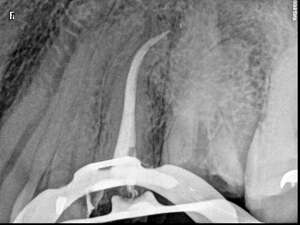

Cas du patient 5

Avant

Après